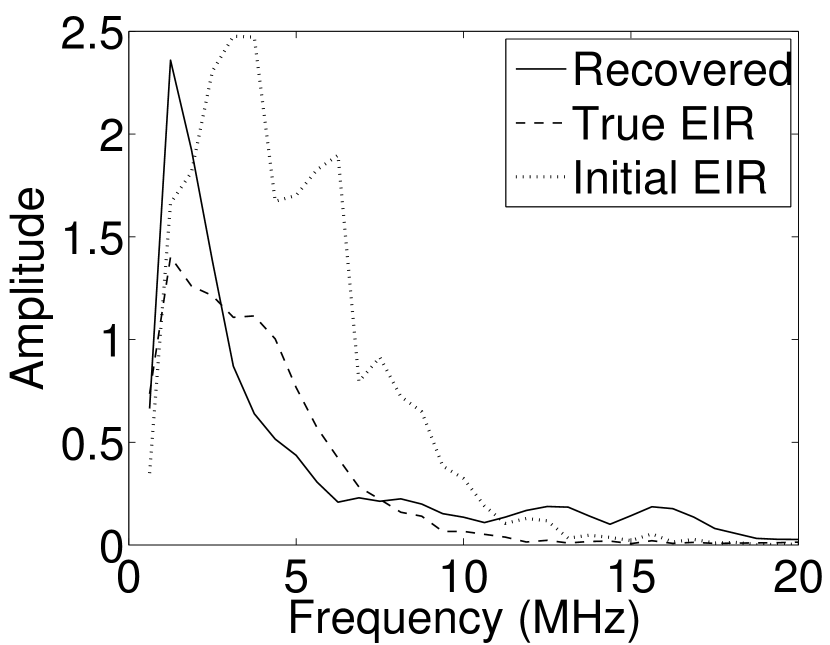

Images reconstructed by use of the VP algorithm with different values of the regularization parameter values are shown in Figure 8. The recovered EIRs and their corresponding Fourier spectra are shown in Figures 9 and 10, respectively. The RMSE values are computed and displayed together with the corresponding images. As expected, the images reconstructed with smaller values of contain higher noise levels, while images using larger possess a reduced noise level. However, larger values of also caused artifacts in the reconstructed images. The same observation can be made for the effect of the regularization parameter on the recovered EIR. One also observes that the reconstructed images and EIRs depend continuously on the regularization parameters and , i.e. small changes in the regularization parameters cause minor changes in the reconstructed images and EIRs.

VI Experimental validation